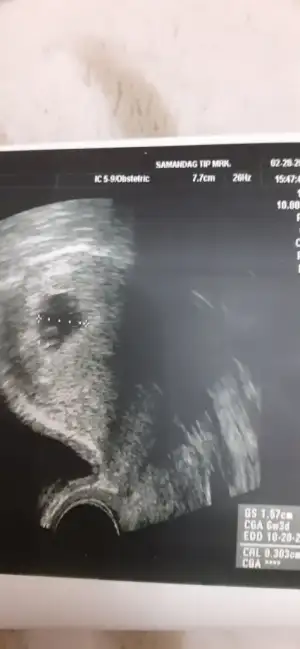

EVET sat 8 ocak :) bebek bile görünmüyordu kesenin içinde. Dün akşam biraz kahverengi lekelenmem oldu. Aslında normal olduğunu okumuştum ama yine de ne olur olmaz doktora gittim. Farklı bi doktordu. Doktor beni yatırdı. Bişey sormadan direk sesi açtı. Ben de şok oldum. :) Dediğiniz gibi çok stresli ve gergindim. İlk hamileliğim olduğu için tecrübesizlik de var tabi. Bişey soramadım heyecanla. Daha önce 10 gün kadar geriden çıkmıştı crl. Şimdi tam 7 haftalık göründü. Sadece 3 gün geriden geliyor. Allahın izniyle o da toparlanır diye inanıyorum :) Dediğim gibi Rabbim herkese hayırlısıyla kucağına almayı nasip etsin :)

Ramzi metodu diye bir sey var bebegin kesedeki vajinal ya da karindan fotosuna gore yorumlaniyor. Ben baktim erkek gozukuyor :) %85 dogruluk payi varmis ornek olarak atayim kendiminkini. Vajinal usg ile cekilmis bir foto ve kesede sağa yerlesmis. Bu aslinda solda oldugu anlamina geliyormus. Solda olanlar da erkek oluyormus.

%85 tutuyormus acilmis konular var bunla ilgili buralarda bakabilirsiniz :) tek onemli nokta vajinal mi abdominal mi bakıldığı :) saglikli olsunlar yeter ki

Vajinal olunca tersini mi düşünmek lazım anlamadım o kısmı. Bu vajinal